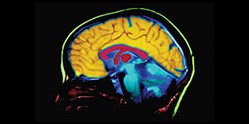

CÓMO FUNCIONA LA SALUD MENTAL

La salud mental es un estado de bienestar en el cual el individuo puede usar sus propias habilidades, recuperarse del estrés rutinario, ser productivo y contribuir a su comunidad, se relaciona con cómo reacciona a las exigencias de la vida y cómo armonizar sus deseos, habilidades, ambiciones, ideas y emociones. Es un problema grave que, si no se trata, acaba provocando trastornos. Pero mantenerlo no es tan simple como dicen algunas personas, especialmente hoy. Los problemas psicológicos y de personalidad hacen que las personas sean más vulnerables a los desequilibrios mentales. Además, las causas biológicas contribuyen a la alteración química de las células cerebrales y aumentan la aparición de la enfermedad.